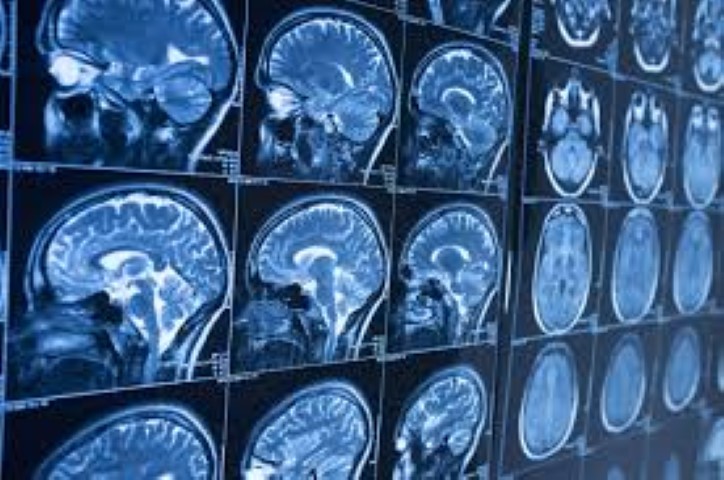

Resonancia Magnética: Precisión, Experiencia y Rapidez en Cada Estudio En nuestra clínica, sabemos…